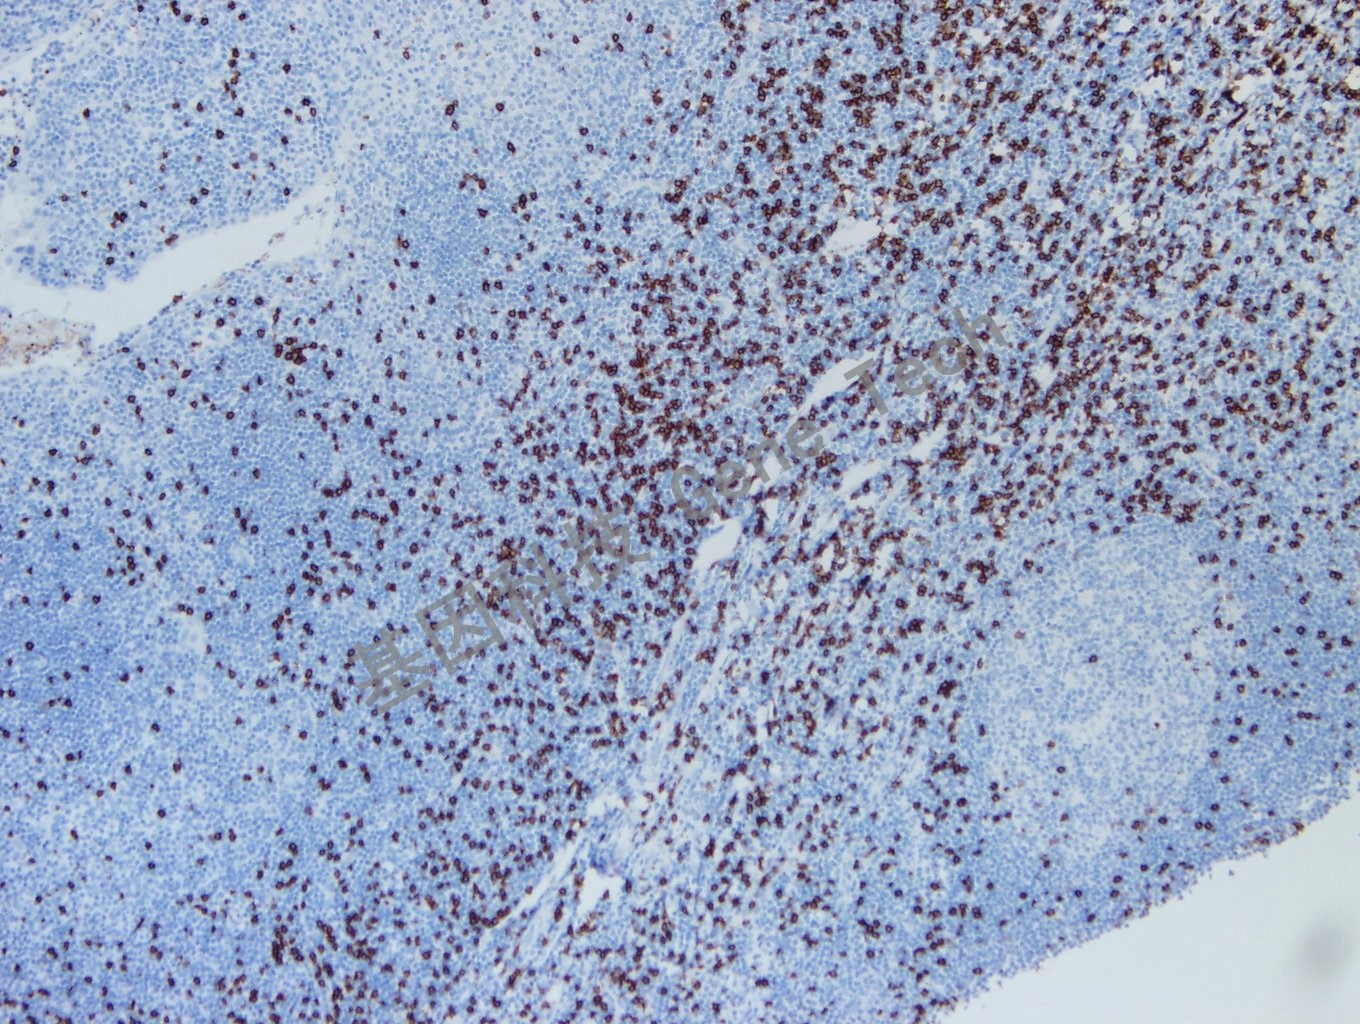

| 克隆號:SP16 | 陽性對照:扁桃體/淋巴結 | 陽性部位:細胞膜 |

| 預處理:高pH熱修復 | 適用:石蠟切片/冰凍切片 | 顯色系統:GTvisionTM |

| 扁桃體石蠟切片,用 CD8(GT2112)染色,細胞膜陽性,DAB 顯色。 | ||